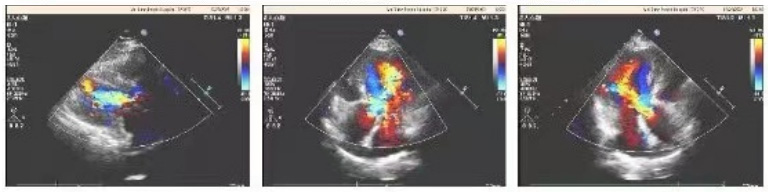

主动脉瓣位瓣架位置固定,瓣叶活动良好,未见赘生物回声,主动脉瓣位生物瓣启闭未见异常,支架与周围组织连接紧密,运动同步,未见瓣周漏,流速1.3m/s。二、三尖瓣口可见少量反流。

孙仕斌教授表示:“这款国产高端的外科生物瓣膜,在瓣叶处理技术上面,可以比肩进口最新一代瓣膜,术后效果显示血流动力学表现更好。从这一案例上来看,跨瓣压差与流速表现都更加优异。与此同时在抗钙化能力、疗法拓展、植入体验等方面推出了前所未有的创新,开创了国产高端生物瓣膜的新品类。在抗钙化能力上,金仕信力X-LINK® 牛心包生物瓣膜采用了行业领先的Micro-EX全封闭抗钙化技术,同时在组织处理和瓣膜保存中封闭了钙化来源,带来耐久性的巨大提升。这种处理大大提高了瓣膜的抗钙化性能和力学性质,从而提升了使用寿命。”